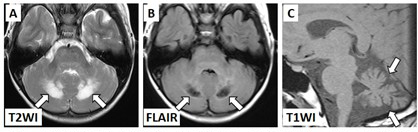

図1に典型的なLCHNDの経過を示します。LCHと診断された時にLCH-NDを発症していることは極めてまれです。多くの場合、LCHと診断されてから3年以上経て、多くの患者さんでは元々のLCHの骨の病変などがなくなっている時期に、脳MRI検査で小脳に左右対称性の異常信号が出現します(図1中、図2A)。

A.小脳虫部の左右対称性T2高信号病変

B.嚢胞状変化

C.著しい小脳萎縮

この状態を臨床的中枢神経変性症(clinicalND)と呼びます(図1右)。このとき脳MRI所見は悪化し、嚢胞状変化(図2B)や脳萎縮(図2C)が現れてきます。 神経症状の進行は個人差が大きく、軽度の運動失調のみで経過する例から数年で寝たきりになる例まであります。